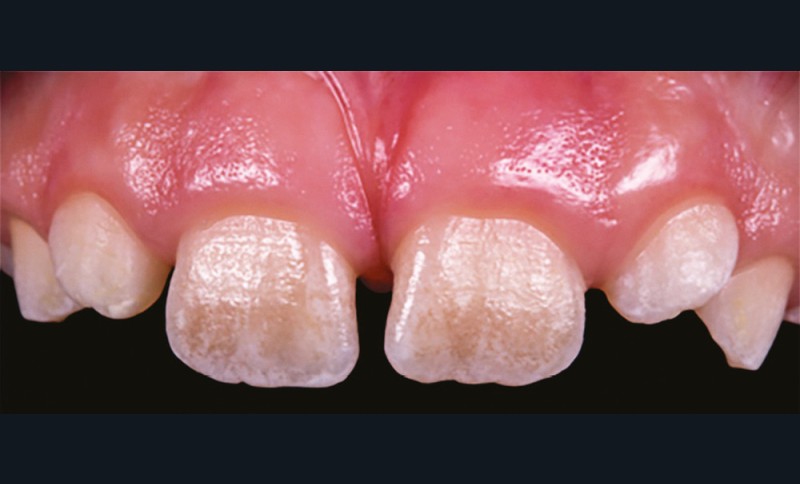

L’amélogenèse imparfaite est le nom donné à un groupe hétérogène de pathologies caractérisées par un défaut inné du développement de l’émail affectant toutes les dents des deux dentures. Ce sont des maladies génétiques dont l’origine est la mutation d’un gène impliqué dans l’amélogenèse. À ce jour, plus de 200 mutations différentes ont été identifiées, ce qui explique des phénotypes très variés [1]. Selon le stade de la maladie, l’émail est hypoplasique (défaut quantitatif), hypominéralisé, ou hypomature (défauts qualitatifs) : il est fin, fragile, tâché ou dyschromique. L’intensité des défauts peut être légère (forme frustre) ou très sévère, allant jusqu’à une absence totale d’émail. Son aspect est altéré par des dyschromies, fractures ou irrégularités de surface (fig. 1-4).